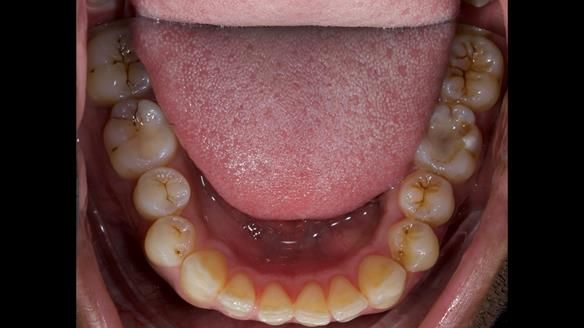

This 34 year old man was referred to me by his general dental practitioner for treatment.

In 2009 (aged 18yrs) an odontogenic myxoma in the upper left maxilla was surgically removed along with the UR2 - UL7 teeth. An acrylic based prosthodontic partial denture/obturator was made was made and fitted post surgery in the NHS hospital system.

Diagnoses

Acrylic based partial denture/obturator had poor, retention and support

Obturator section was in poor condition - unhygienic

Adams clasp were causing inflammation of the gingival margins

Clasp on the UR3 was visible resulting in poor appearance

Reduced lip support on the upper left area

Sloping incisal plane - running up on the left

Increased wear of the natural dentition